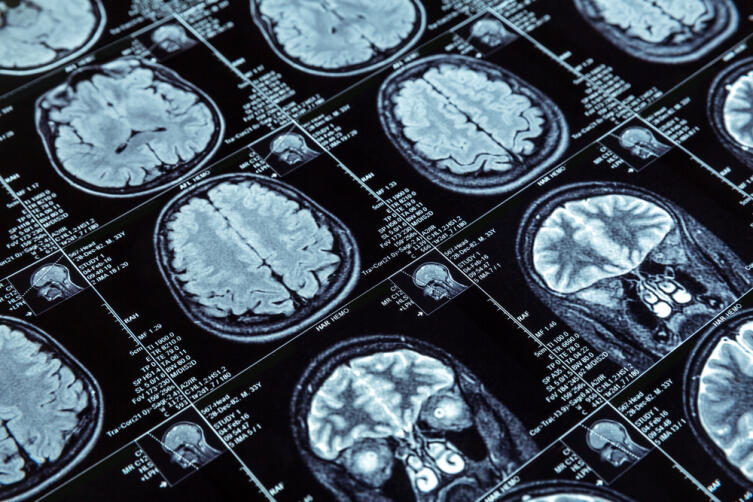

Магнитно-резонансная томография — эффективная диагностическая процедура, позволяющая получать отчетливое изображение в различных плоскостях, не перемещая при этом пациента, не меняя его положения. Эта особенность бывает очень ценной, например, при диагностике повреждений в случае тяжелых травм.

В отличие от компьютерной томографии (КТ), метод позволяет визуализировать не только рентгеноконтрастные ткани и объекты. На снимках, сделанных при помощи МРТ, видна структура и мягких тканей.

Для еще более подробного изучения сосудистого русла может быть проведено сосудистое контрастирование. Эта методика информативна, в частности, при обнаружении, например, сосудистых аневризм и (или) мальформаций.